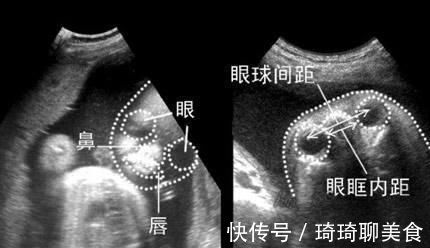

四维彩超宝宝鼻子大,是怎么回事?

四维彩超为什么鼻子大呢?一般有下面几种原因。

成像原理导致的

四维成像的远离不是小孔成像,不是拍的时机照片,而是在二维基础上,加上时间维度,用电脑软件合成的图像。四维彩超会将立体模式进行重建,将胎儿的面部结构更为清晰、更为直观地显示出来,有利于将可靠的依据提供给胎儿面部畸形筛查。